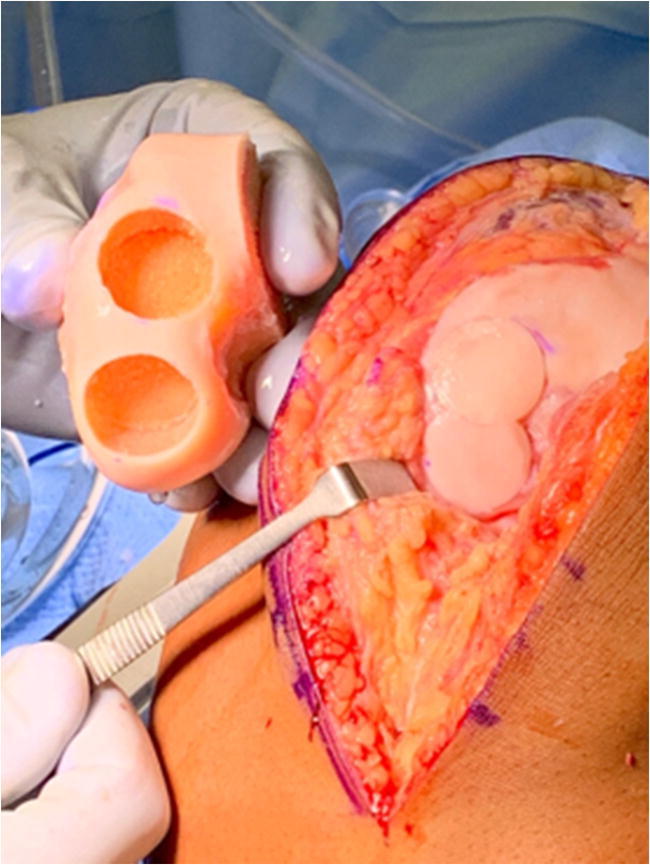

Donor grafts are matched based on radiographic, CT, or MRI measurements depending upon the graft supplier. Figure 3 demonstrates a donor hemicondyle that has been matched to the recipient for osteochondral allograft transplantation. An arthrotomy is performed, and the OCD visualized and the appropriately sized allograft are determined. A guide pin is placed perpendicular to the recipient articular surface, the cartilage margin is scored using a size matched tool, and then a reamer is used to debride the selected area of bone and cartilage. Reaming is performed to a depth of bleeding subchondral bone, with ideal bone thickness of 6–9 mm. Donor plug bone thickness less than 5 mm has been associated with an increased odds ratio of cystic changes, while thickness greater than 9 mm is associated with residual osseous clefts, assign of incomplete osseous incorporation [42••]. Next, the donor hemicondyle is assessed to select the area which most closely matches the contour, and a plug of corresponding size is harvested, again ensuring the dowel is reamed perpendicular to the articular surface. Recipient site depths are measured in each quadrant, and the donor graft is likewise marked with these same dimensions and trimmed to appropriate depth. Pulse lavage of the donor dowel has classically been described as a means of removing residual donor marrow elements, although the most recent evidence suggests this is no more effective than no lavage [43••]. The donor graft is then inserted into the recipient site with matching orientation and a press fit. Great care should be taken to dilate the recipient site as forceful insertion of the graft may decrease chondrocyte viability. A moist sponge applied over the graft if light impaction is needed helps dissipate forces on the graft. In large OCDs, additional grafts may be added in a “snowman technique” of interdigitating grafts (Fig. 4) [44].

Fig. 4.

Donor hemicondyle and recipient following osteochondral allograft transplantion to the lateral femoral condyle using a “snowman” technique to interdigitate allograft dowels